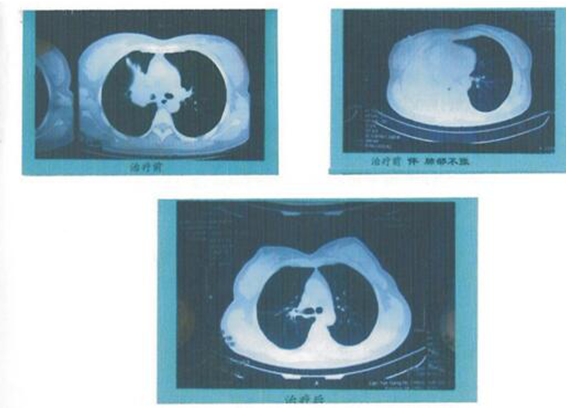

同时已将中医名药东南1号近期申办,由军制号转为国家药准字号。因其生产工艺采用世界先进的纳米低温旋转分离技术制造的小分子药物,药物具有超强的穿透性,能快速透入机体组织,作用于肿瘤病灶,与肿瘤细胞DNA相结合,阻止其复制,抑制肿瘤细胞生长,软化增生组织特点,故首批药物在临床使用后见到临床症状迅速缓解,病灶缩小,而逐渐消退,更重要的是纯中药制剂,它不会给身体带来任何不良反应,不会产生任何抗药性,故为肠胃道癌理想的治疗药物,将给广大病人带来福音,尤其是晚期患者带来生的希望。 造福肺癌患者 开创中西医结合治疗肺癌新时代 用创新守护生命,高教授和他团队没有停下开拓创新的脚步。在他们手中,创新就是战胜病魔、守护生命的利器!肺癌一直是“头号”恶性肿瘤,为探索肺癌患者生存期瓶颈,高教授团队根据肺癌病理类型(腺癌或麟癌),结合中医临床症候,辨病与辨症相结合,并针对肺癌肺内转移,纵隔转移,并发胸腔积液,心包积液和脑转移等,与二军大,全国海洋生物研究所一起研制发明了全球第一代靶向药:肿瘤血管生长抑制因子——鲨威1号,从2010年开始这种新的药物治疗方法已经为肺癌病人临床一线的治疗,多数病人无需住院化疗可获病灶消失(缓解),不仅临床无明显副反应且疗效较传统化疗高2倍,对化疗治疗失败或耐药病人也可获效,长期中药巩固维持治疗,可有效防止肺癌复发转移,使病人长期生存。经中西医结合治疗一些病例仅14天—2个月复查病灶消失,缓解,病灶消失以后经中药长期巩固维持治疗,生存期已达1-2年以上,最长生存期达22年以上。 如肺腺癌脑转移患者沈阿双,女,65岁,2012年4月因肺腺癌脑转移伴脑梗,右侧肢体偏瘫,不能活动,慕名前来,经应用中药补阳还伍汤,蛇六谷联合全脑放疗十易瑞沙,及可透过血脑屏障,治疗肺癌脑转移的鸦胆子油治疗,肢体功能逐渐恢复,至2012年6月20日能自由行走,脑CT示脑转移灶消失,以后长期以中药肺癌1号方十易瑞沙及鸦胆子油乳巩固治疗,至今情况良好已3年以上。 右上肺鳞癌患者孙雪妮,连云港粮食局职工,CT示右上肺鳞癌,给予GP方案化疗,病灶进展,伴肺不张,经应用三参莲苡南星汤合牛黄醒消丸,及特罗凯,临床症状消失,CT复查右上肺占位消失。(附CT)

肺鳞癌患者孟明星,55岁,连云港干部,因咳嗽,咳痰带血。2014年2月经CT发现右肺占位(中央型肺癌)气管镜示:右肺下叶见一菜花样新生物2×3cm,病理为鳞状细胞癌,因病灶贴近心脏,无法手术。于2014年3月3日闻名前来,经应用中药三参莲苡南星汤,牛黄醒消丸,平消胶囊,联合伽玛刀及特罗凯中西医结合治疗,至2014年3月17日模拟CT示病灶完全消失。一般情况良好,临床无症状,血象正常,已上班工作。(附治疗前后CT片) 注:病人经中药+靶向+伽马刀中西医结合治疗,仅14天就获病灶消失,这是前所未有的奇迹,提示我们要探索最优化组合疗法。